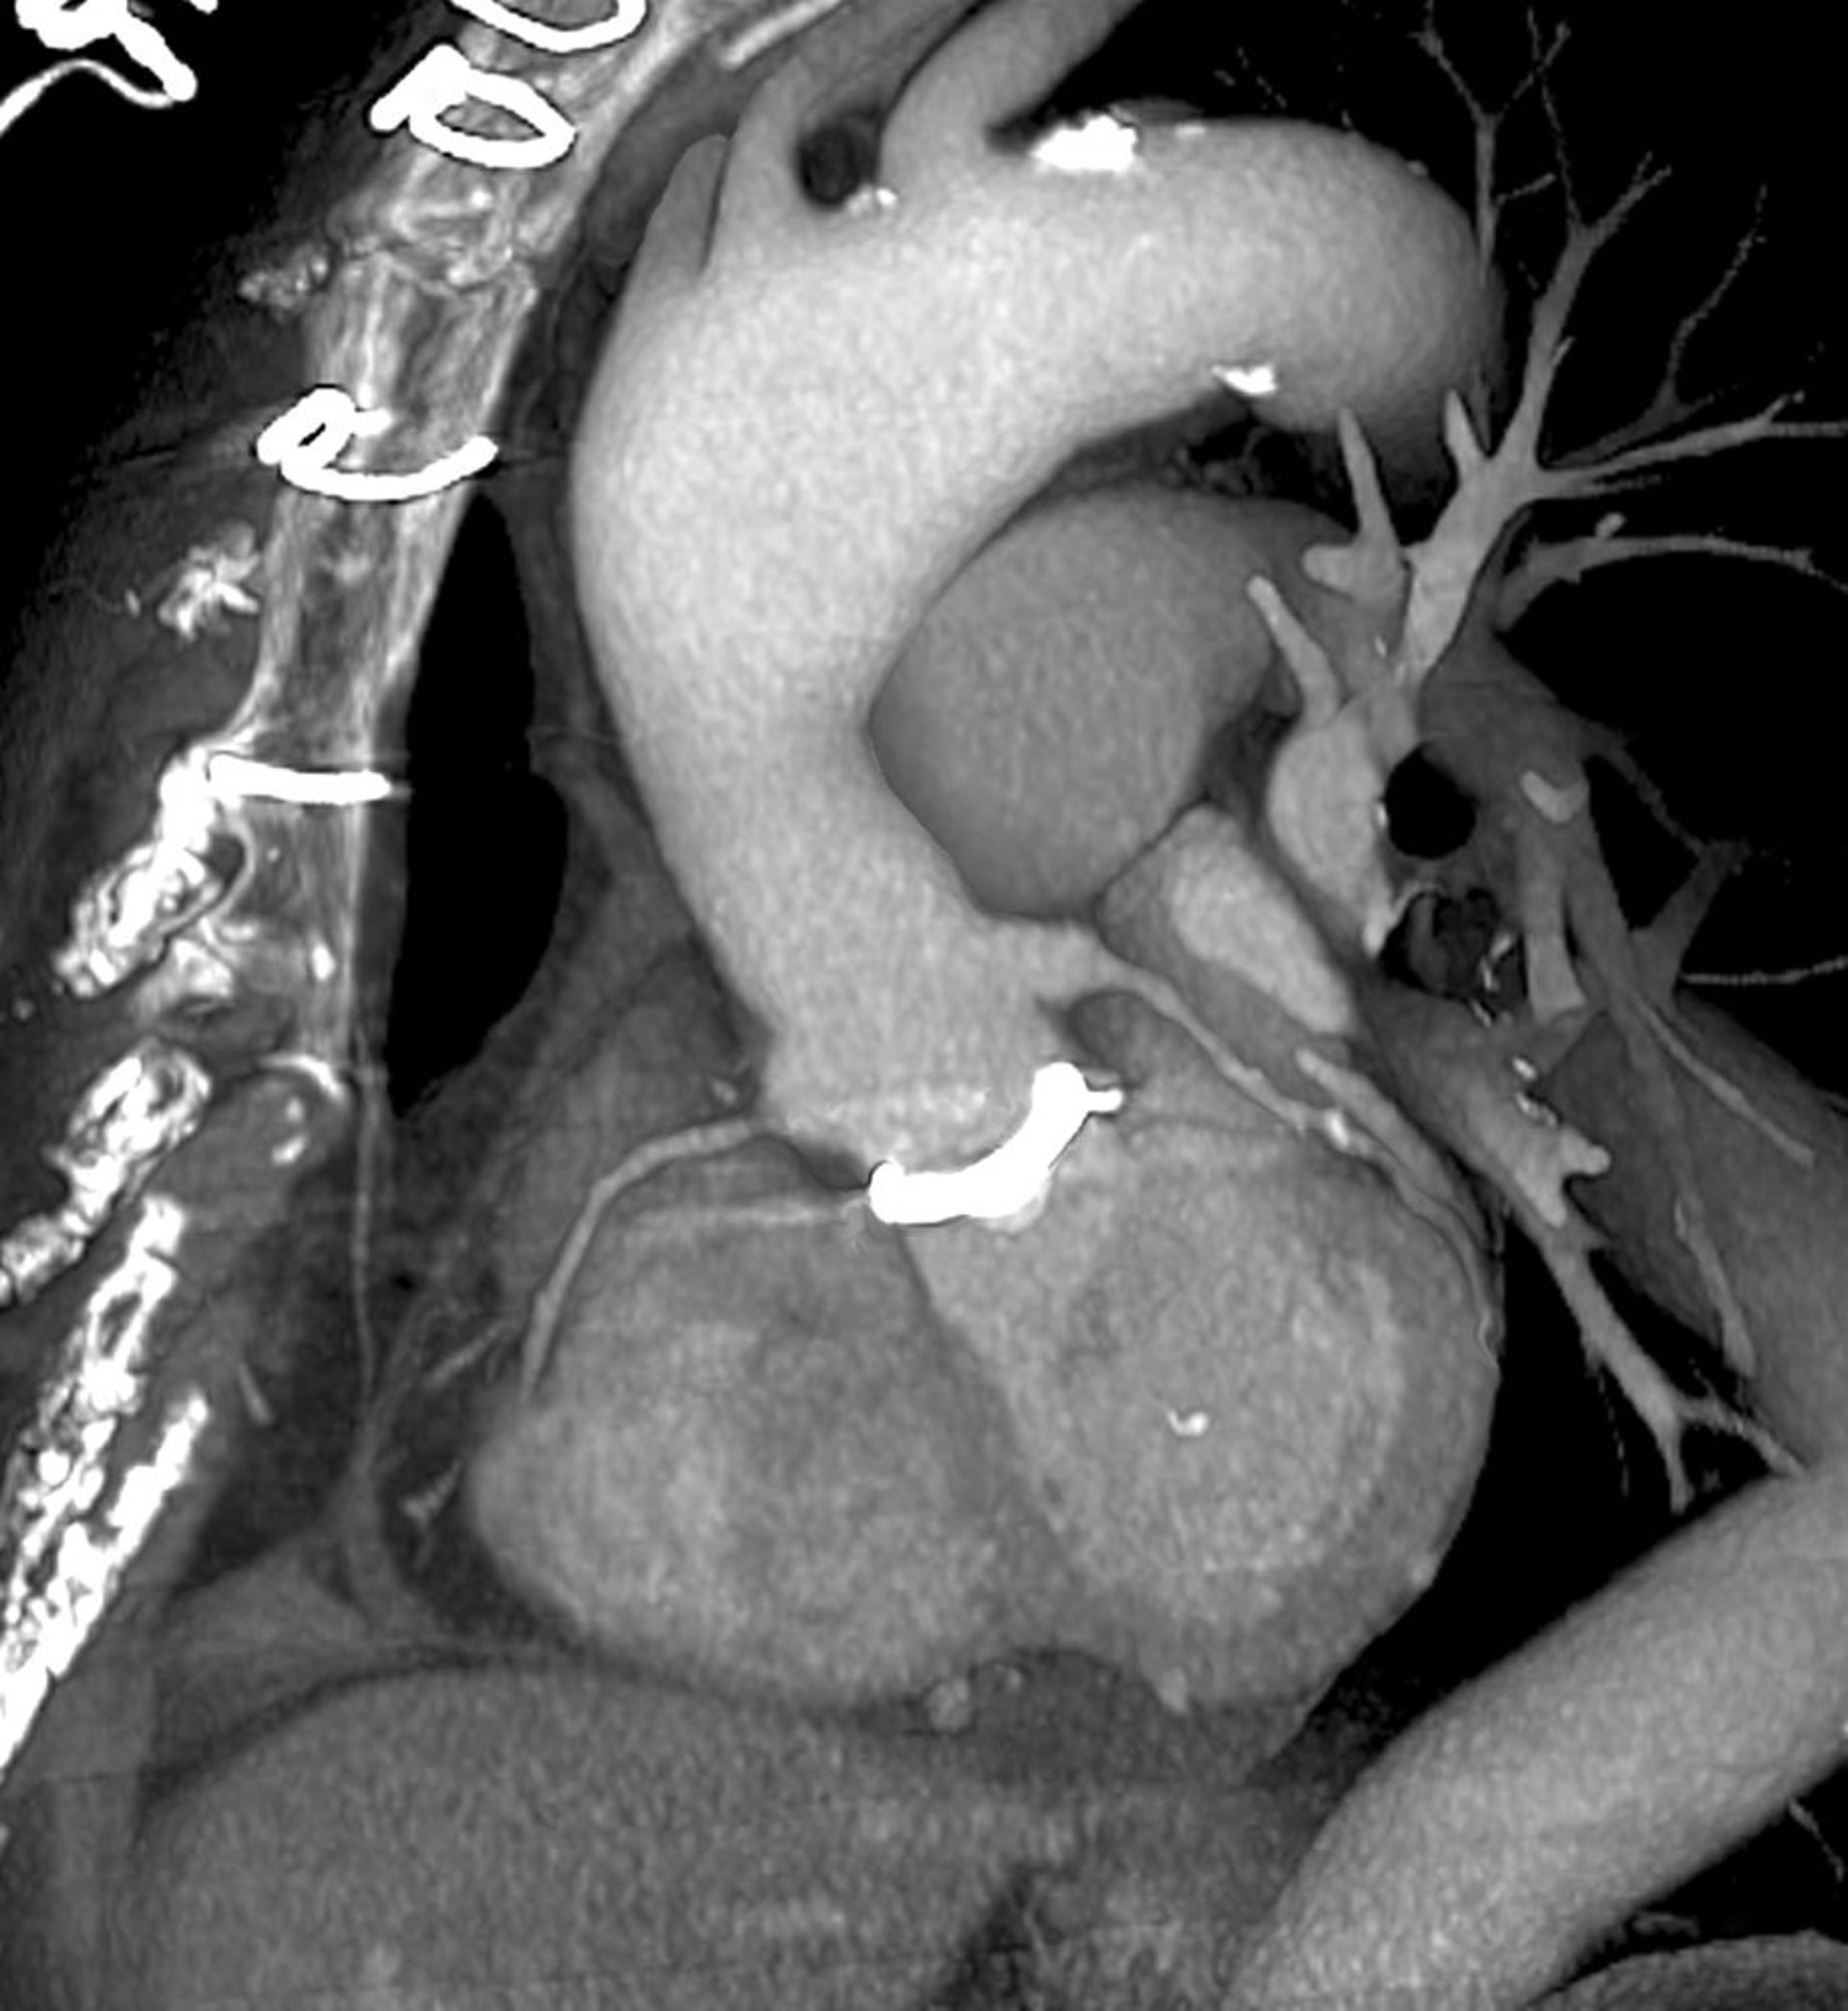

TC cardiaca (scansione 3D della protesi valvolare cardiaca)

Questa è una incidenza obliqua del lato sinistro, guardando verso la parte anteriore del torace (a sinistra). La protesi valvolare cardiaca (bianca) è visibile al centro, dove l'aorta (centro in alto) incontra il cuore (centro in basso). I punti utilizzati per chiudere il torace sono visibili in alto a sinistra.

ZEPHYR/SCIENCE PHOTO LIBRARY